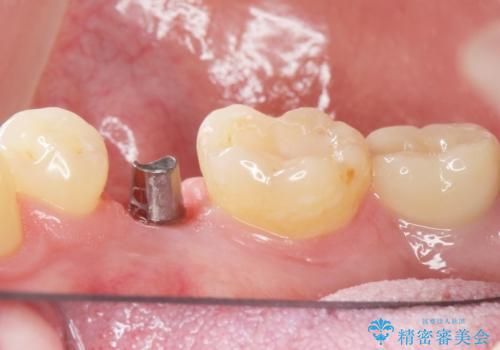

予算を抑えてしっかりとしたインプラント治療 30代男性

- 奥歯(右下5)のインプラントをご希望し来院された患者様です。

なるべく低予算でとのご希望により、アルファタイトインプラント(保証期間:3年)による治療を行いました。

インプラントの種類:アルファタイト

クラウンの種類:オールセラミッククラウン スタンダード